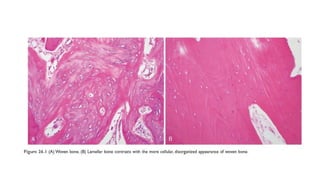

• Bone matrix can be woven or lamellar.

• Woven bone is produced rapidly (during fetal development or fracture

repair) and is always abnormal in adults, but its presence is not specific for

any particular disease.